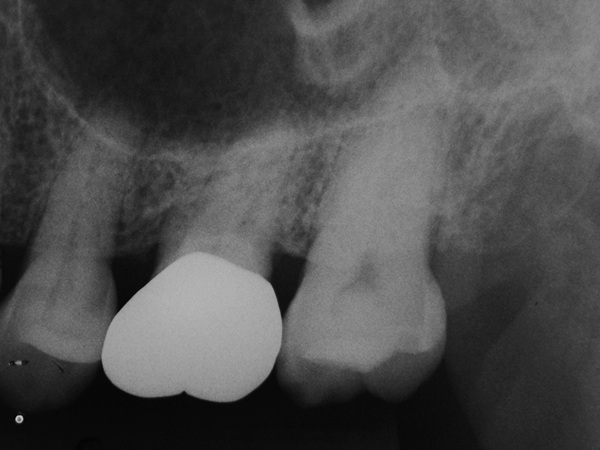

患歯(矢印)にヒビが入っているかレントゲン診査では分かりませんが、大きな病巣?は確認できません。